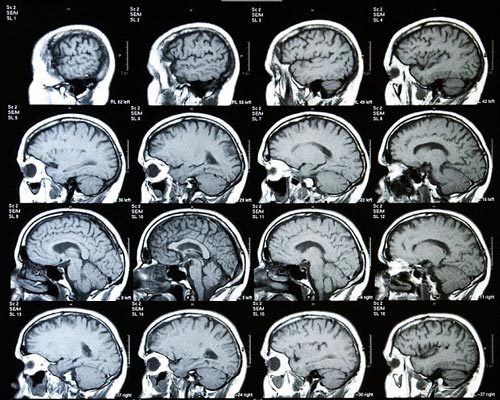

Theo báo cáo nghiên cứu đăng tải trên tạp chí PNAS, các chuyên gia đã sử dụng kỹ thuật chụp cộng hưởng từ để xem xét những kết nối nhất định trong bộ não của 66 đứa trẻ. 47 bé trong số đó chào đời trước tuần thứ 33 của thai kỳ và do đó đối mặt với nguy cơ cao bị sút kém về thần kinh. 19 bé còn lại được sinh ra đủ ngày, đủ tháng.

Các kết nối não được kiểm tra nằm giữa vùng đồi não và vỏ não. Đây là những kết nối phát triển nhanh chóng trong giai đoạn một trẻ sinh non được chăm sóc trong khoa sơ sinh của bệnh viện.

Nhóm nghiên cứu phát hiện, những trẻ sinh đủ ngày, đủ tháng, tức là trong giới hạn từ tuần thai thứ 37 tới 42, có cấu trúc kết nối não rất giống ở người trưởng thành. Nó củng cố thêm các bằng chứng hiện có khẳng định, mạng lưới kết nối của bộ não người đã hoàn chỉnh lúc chào đời.

Tuy nhiên, những trẻ sơ sinh đẻ non trước tuần thai thứ 33 được phát hiện có ít kết nối hơn giữa vùng gò đồi và các khu vực nhất định thuộc vùng vỏ não chuyên hỗ trợ các chức năng nhận thức cao hơn. Tuy nhiên, chúng có kết nối lớn hơn giữa vùng gò đồi với một khu vực thuộc vỏ não thị giác tiên khởi, liên quan đến việc xử lý các tín hiệu từ mặt, môi, hàm lưỡi và cổ họng.

Đứa trẻ chào đời càng thiếu tháng, sự khác biệt trong kiểu kết nối não của chúng so với những trẻ sinh đủ ngày, đủ tháng càng lớn.